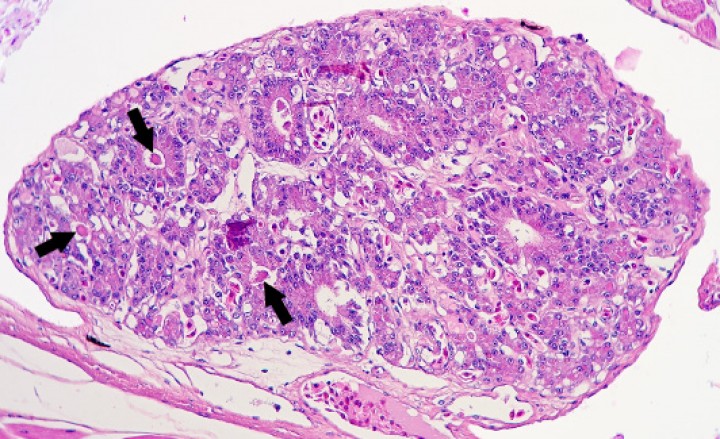

Se observaron 8 neoplasias, diagnosticadas en 6 de los 131 (4,6%) anfibios. Dos correspondían a adenocarcinomas sin evidencias de metástasis: uno intestinal en una rana dardo verdinegra (Dendrobates auratus) (Fig. 8), y otro en un tejido no identificable en un sapo buey (Rhinella schneideri); este último mostraba, además, hemangiomas en el pulmón (Fig. 9). El adenocarcinoma intestinal de la rana dardo verdinegra (Dendrobates auratus) consistía en una proliferación mal delimitada y no encapsulada de enterocitos que formaban criptas y glándulas variablemente dilatadas o, raramente, nidos diminutos compactos que invadían de forma amplia todas las capas del segmento intestinal afectado (Fig. 8) y mostraban anisocitosis, anisocariosis, pleomorfismo y anaplasia bajos a moderados, sin actividad mitótica aparente. Otros 3 anfibios padecieron neoplasias hematopoyéticas: un linfoma multicéntrico con componente epiteliotrópico en una rana tomate (Fig. 10) y dos neoplasias de células redondas no identificables de forma clara mediante la tinción rutinaria en un sapillo balear (Alytes muletensis) y un axolote (Ambystoma mexicanum). Otro sapillo balear (Alytes muletensis) mostraba una proliferación multicéntrica benigna de epitelio renal tubular (Fig. 11) organizado en estructuras tubulares, papilares y quísticas (Fig. 12), compatible con adenomatosis renal (adenomas múltiples); se observó atipia celular en escasas células neoplásicas y en células epiteliales de túbulos no neoplásicos. Adicionalmente, en este sapillo balear (Alytes muletensis) se apreció un foco hepático bien delimitado y no encapsulado de proliferación de hepatocitos compatible con hiperplasia nodular o un hepatoma; la ausencia de tríadas portales dentro de esta neoplasia es compatible con un hepatoma (Fig. 13).

<p>Riñón; sapillo balear (<em>Alytes muletensis</em>). La sección de riñón del sapillo en la Figura 11 está casi completamente reemplazada por un adenoma con zonas papilares densas (P) y zonas quísticas (Q), que comprime el tejido renal no neoplásico restante (cabezas de flecha). Hematoxilina-eosina, x48.</p>

Figura 12

Riñón; sapillo balear (Alytes muletensis). La sección de riñón del sapillo en la Figura 11 está casi completamente reemplazada por un adenoma con zonas papilares densas (P) y zonas quísticas (Q), que comprime el tejido renal no neoplásico restante (cabezas de flecha). Hematoxilina-eosina, x48.

Por lo que respecta a las enfermedades neoplásicas, destaca su baja frecuencia en este estudio, con solo 6 de 131 anfibios afectados. De las neoplasias diagnosticadas, el linfoma es el más frecuentemente descrito en anfibios.[ Stacy BA, Parker JM. Amphibian oncology. Vet Clin Exot Anim 2004; 7(3):673-695. [PubMed] ] En cuanto a los adenocarcinomas intestinales, se han documentado raramente en anfibios en la bibliografía,[ Stacy BA, Parker JM. Amphibian oncology. Vet Clin Exot Anim 2004; 7(3):673-695. [PubMed] , Vaughan RJ, Vitali SD, Payne KL, Eden PA. A splendid tree frog with edema syndrome and intestinal adenocarcinoma. Vet Clin North Am Exot Anim Pract 2006; 9(3):583-587. [PubMed] ] aunque existe un estudio reciente de la presentación de múltiples casos en una colonia de ranas lecheras amazónicas (Trachycephalus resinifictrix).[ López J, Barbón AR, Smithyman J, et al. High prevalence of intestinal adenocarcinoma in a captive population of amazon milk frog (Trachycephalus resinifictrix). J Zoo Wildl Med 2016; 47(4):1061-1068. [PubMed] ] En el presente estudio se observó un caso de adenomatosis renal y hepatoma en un sapillo balear (Alytes muletensis); los adenomas y adenomatosis renales no están descritos en la bibliografía de anfibios, a diferencia de los adenocarcinomas renales.[ Stacy BA, Parker JM. Amphibian oncology. Vet Clin Exot Anim 2004; 7(3):673-695. [PubMed] ]